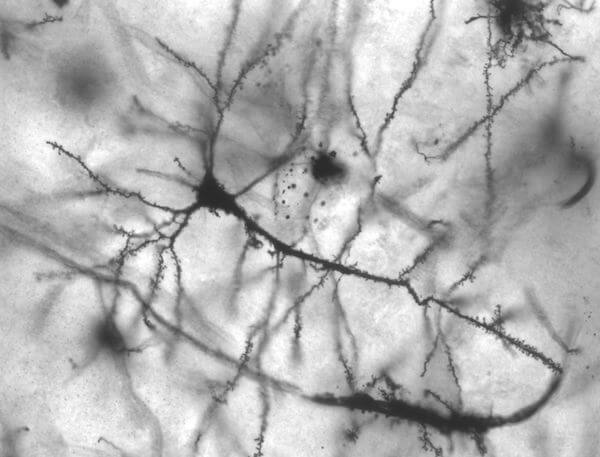

A brandet úgy képzeld el, mint egy hatalmas neuronhálózatot:

A márkáddal új neuront hozol létre, amihez asszociációkat kapcsolsz (más neuronokat).

Minél több és szorosabb asszociációt hozol létre, annál hamarabb jut az emberek eszébe a terméked a brand megpillantásakor vagy megemlítésekor.